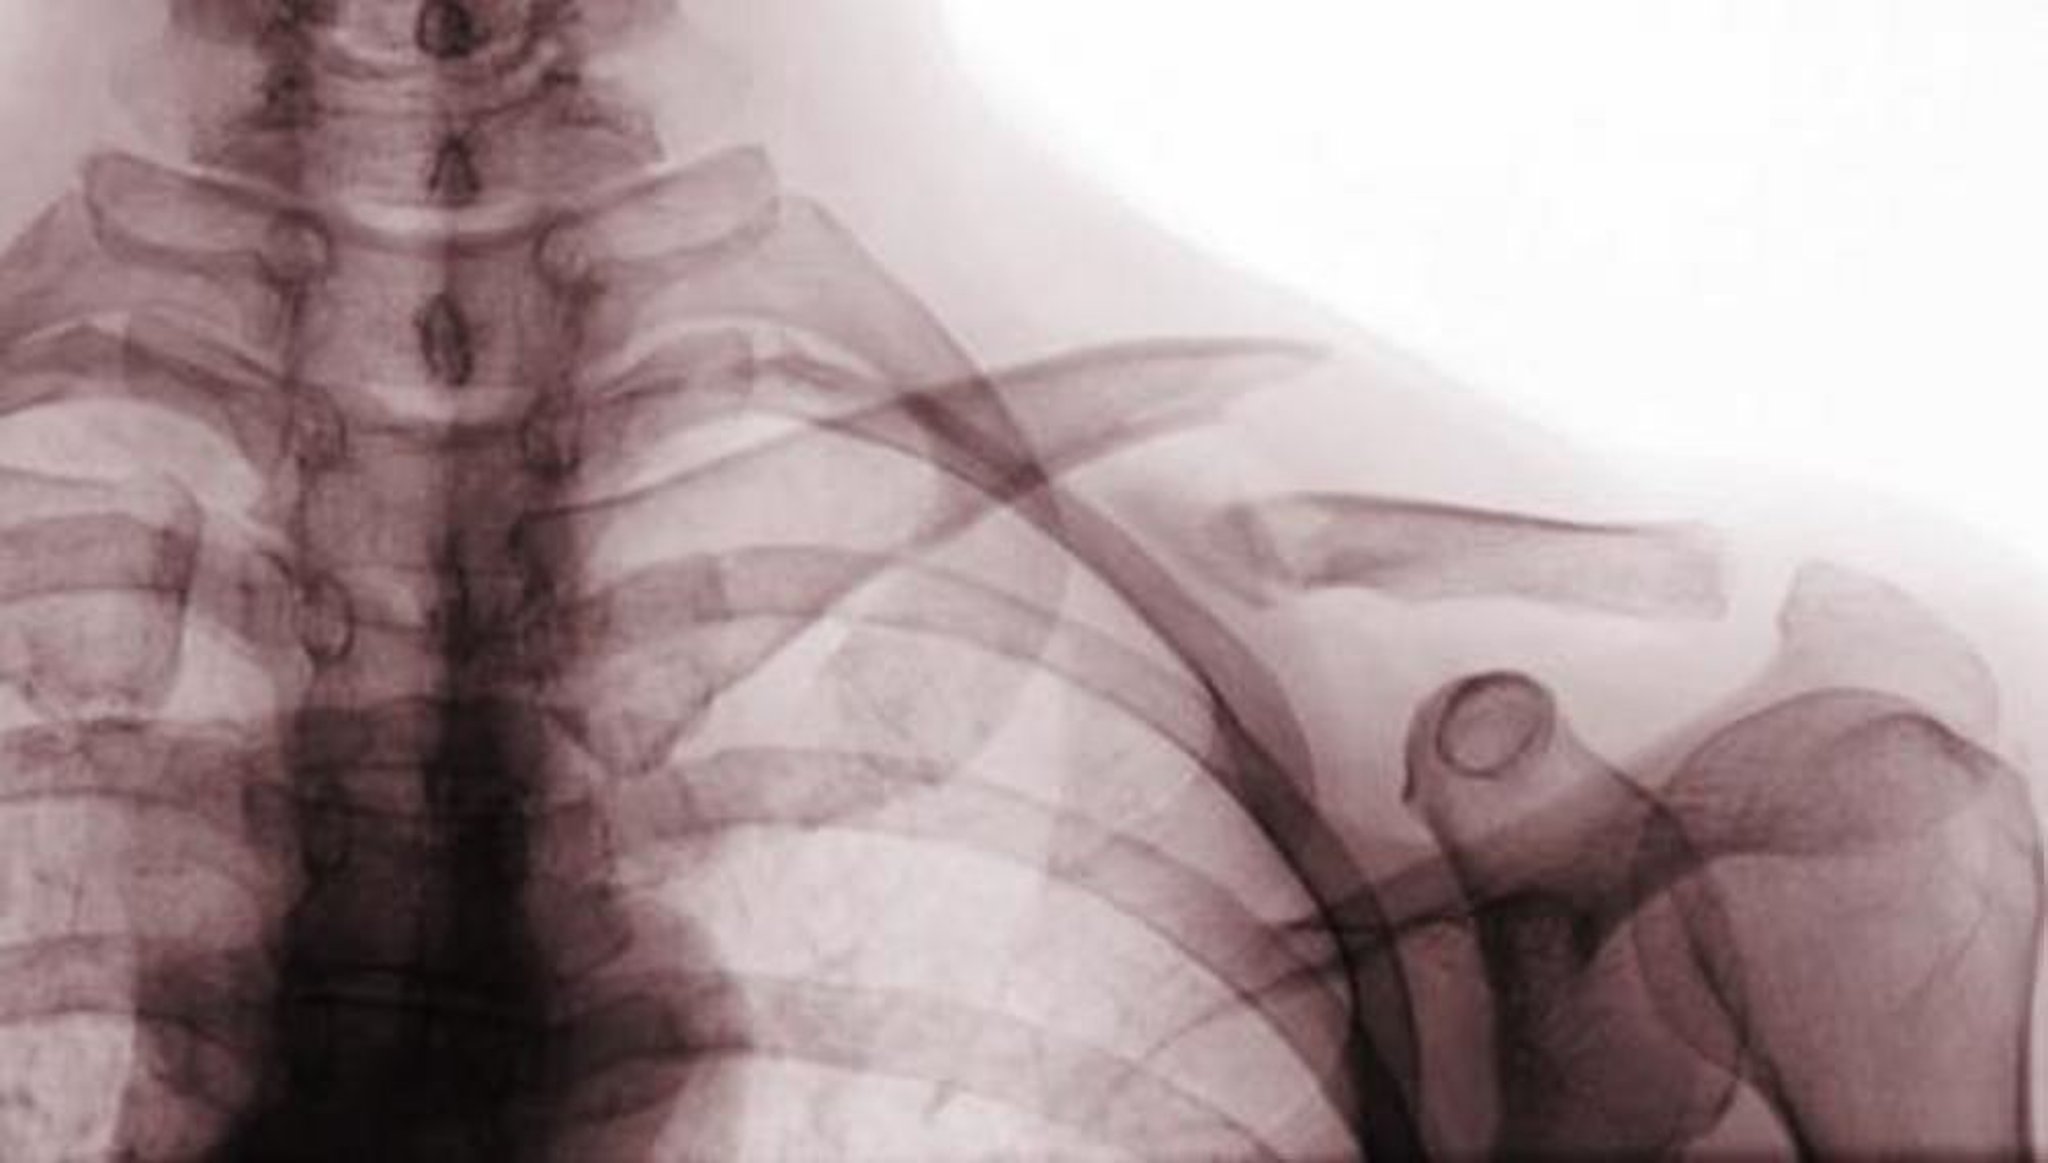

• Tipo III: coinvolge la superficie intra-articolare dell'articolazione acromioclavicolare, aumentando così il rischio di artrosi (vedi figura Classe B delle fratture della clavicola)

Classe B delle fratture della clavicola